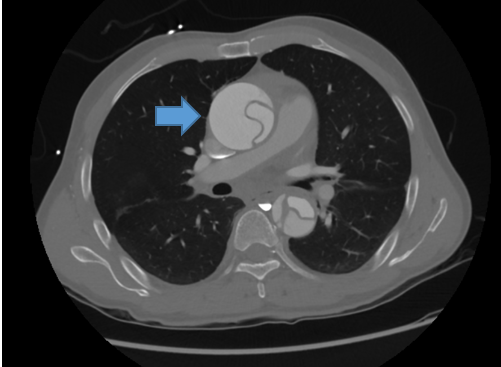

대동맥에 주로 발생하는 질환으로는 대동맥박리, 대동맥류를 들 수 있다. 대동맥박리는 대동맥을 이루는 3층의 막 중 가장 안쪽에 위치한 내막에 미세한 파열이 발생하면서 생기는 질환이다. 고혈압, 마르팡증후군 같이 유전적 원인으로 인해 대동맥의 혈액이 내막과 중막 사이로 고이고 층의 분리가 일어나 발생한다. 대동맥의 층이 분리되면 피가 고인 부분에 ‘가성 내강’이 형성된다. 그 결과 정상적으로 혈류를 보내고 있는 공간인 ‘진성 내강’이 좁아지고 주요 장기에서 피가 부족한 허혈이 생긴다. 얇아져 있는 가성 내강에 혈류가 계속 고여 대동맥 파열로 이어질 수도 있다. 따라서 대동맥박리가 발생한 경우 발생 혈관의 위치와 허혈 증상의 동반 여부가 치료 방향을 결정하는데 매우 중요한다.

대동맥박리는 발생 위치에 따라 크게 A형과 B형의 2가지로 나뉜다. A형 대동맥박리는 심장에 가까운 상행대동맥, 대동맥궁에 대동맥 박리가 있는 경우다. 심장이나 뇌에 허혈을 일으킬 가능성이 높은 데다 혈압이 높은 부위이기 때문에 대동맥 파열로 진행할 위험이 높다. 증상 발현 후 48시간 이내 사망할 확률이 50% 이상일 정도로 매우 위험한 상황이다. A형 박리는 흉통이나 실신, 뇌경색 등의 증상으로 발견되는 경우가 많다. 만약 이같은 증상이 있다면 지체없이 응급실로 내원해야 한다. 컴퓨터단층(CT) 검사 결과 A형 대동맥박리가 맞다면 즉시 응급수술이 필요하다.

대동맥 박리가 하행 대동맥, 복부대동맥에만 발생한 경우 B형 대동맥박리로 분류된다. 등에 갑작스럽게 발생한 통증이나 복부 통증, 다리 마비 등이 주요 증상이다. A형 박리에 비해 사망률이 높지는 않은데 복부 장기, 다리 허혈로 인해 허혈성 또는 괴사성 장염이 생기거나 중증 하지 허혈로 합병증이 생길 수 있다. 이같은 합병증이 의심될 땐 수술 또는 스텐트 시술 등을 통한 응급 치료가 필요하다. B형 박리는 언제든지 박리 부위가 심장이나 뇌혈관 쪽으로 진행돼 A형 박리로 변할 수 있다. 입원 후 혈압 조절과 경과 관찰이 반드시 뒤따라야 하는 이유다. 대동맥박리는 CT 촬영을 통해 박리 유무 및 발생 부위를 쉽게 진단 할 수 있는 만큼 증상이 의심되는 경우 즉각 병원에 내원하는 것이 가장 중요하다.